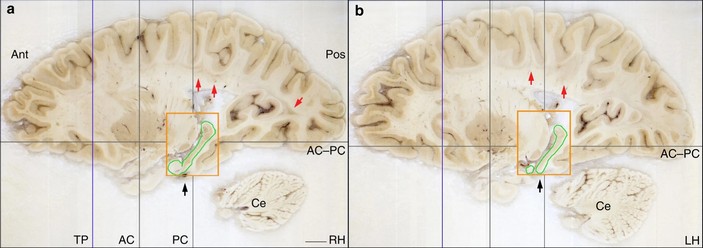

Срезы правого (a) и левого (b) полушарий мозга Г.М. Оранжевый прямоугольник ограничивает часть неповрежденного гиппокампа (выделена зеленым). Изображение из статьи J. Annese et al., 2014. Postmortem examination of patient H.M.’s brain based on histological sectioning and digital 3D reconstruction